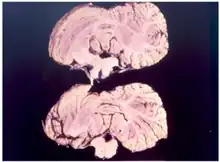

Kuru is a rare, incurable, and fatal neurodegenerative disorder that was formerly common among the Fore people of Papua New Guinea. Kuru is a form of transmissible spongiform encephalopathy (TSE) caused by the transmission of abnormally folded proteins (prions), which leads to symptoms such as tremors and loss of coordination from neurodegeneration.

Kuru, a transmissible spongiform encephalopathy, is a disease of the nervous system that causes physiological and neurological effects which ultimately lead to death. It is characterized by progressive cerebellar ataxia, or loss of coordination and control over muscle movements.[11][12]

Kuru is diagnosed by reviewing the patient's history of cerebellar signs and symptoms, performing neurological exams, and excluding other neurological diseases during exams.[15] The symptoms evaluated are typically coordination issues and involuntary muscle movements, but these markers can be confused with other diseases that affect the nervous and muscle system; physical scans are often required to differentiate Kuru from other disorders.[26][27] There is no laboratory test to determine the presence of Kuru, except for postmortem evaluation of central nervous system (CNS) tissues, so diagnoses are achieved by eliminating other possible disorders.